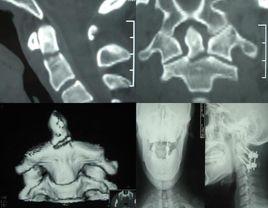

頸椎雙側關節突關節脫位是典型的屈曲性損傷,可以發生在頸2至胸1之間的任何節段,但以頸4以下節段最多見。

本病多見於高處跌落,頭頸部撞擊地面,或重物直接襲擊,致枕頸部受到屈曲性暴力作用,揮鞭樣損傷也可造成脫位,在乘坐高速行駛的車輛聚然剎車時,頭頸部因慣性作用則猛烈屈曲,當頭頸部遭受屈曲暴力時,頸椎活動單位的支點位於椎間盤中央偏後部,由於頸椎的小關節突關節面平坦,且與水平面呈45°交角,驟然屈曲的外方,引起上位頸椎的下關節突前移並將關節囊撕裂,而後向後上方翹起,隨著外力的繼續作用和頭顱重量的慣性作用,已移位的下關節突繼續向前滑動,整個上位椎體也隨之前移,作用力消失後,因頸部肌肉收縮作用,可形成三種狀態:一是隨之復位,日後可有頸椎不穩症或傷後呈半脫位狀態;二是頸椎脫位呈彈性固定,上下關節突關節相互依託,形成頂對頂的“棲息”狀態;三是上位椎體下關節突越過了下方椎體的上關節突,形成小關節突背靠背的形態,即所謂的“交鎖”狀態。